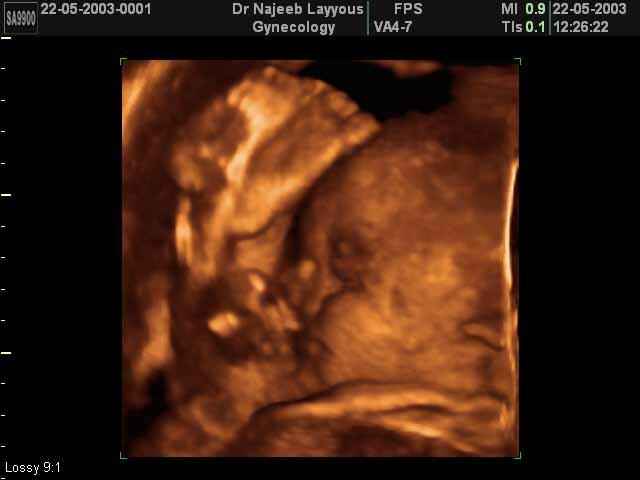

- 3D Fetal Profile Ultrasound Scan Photos

3D Fetal Profile Ultrasound Scan Photos | Dr N Layyous